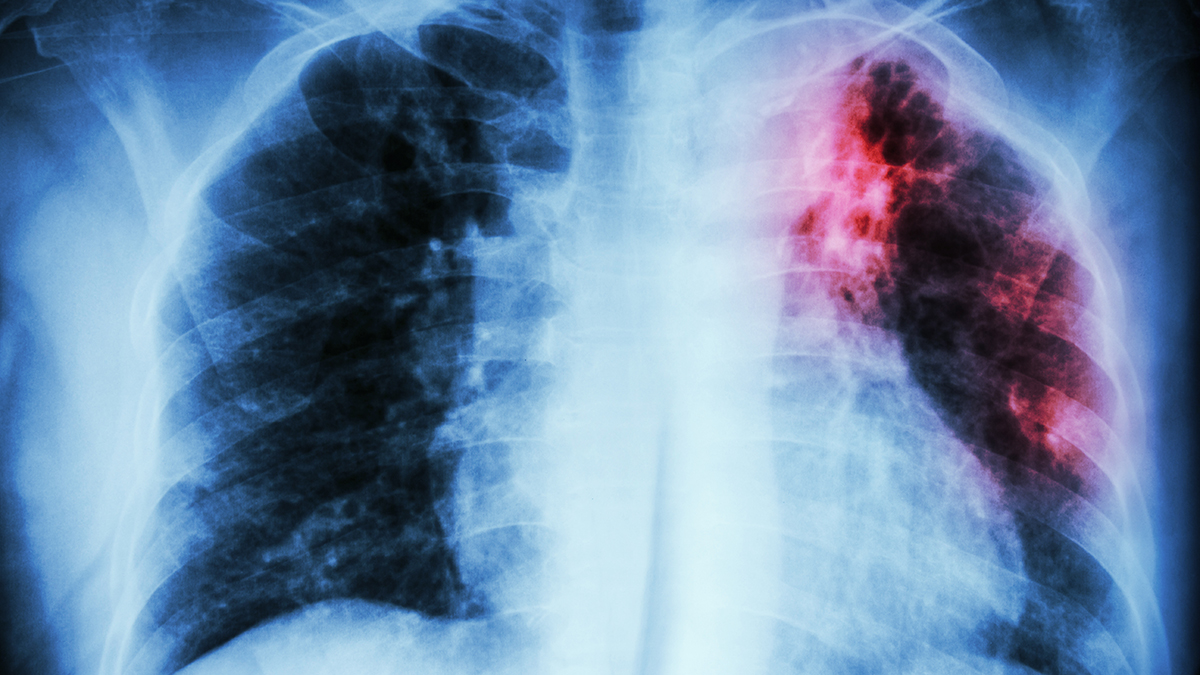

Врач Вознесенский рассказал о возможных последствиях нового штамма туберкулеза

В России есть все современные лекарства для борьбы с новым штаммом туберкулеза, который распространяется в Великобритании. Об этом в субботу, 16 марта, сообщил кандидат медицинских наук, врач-инфекционист Сергей Вознесенский.

По его словам, новая мутация вируса может быть вовсе не так опасна, как о ней говорят в западных СМИ. Такая болезнь далеко не всегда протекает тяжело. Чтобы избежать осложнений, следует укреплять иммунитет, избегать переохлаждения, недоедания и чрезмерных физических нагрузок.

Единственной опасностью может быть устойчивость нового штамма к антибиотикам, однако такое свойство чаще всего встречается у других бактериальных инфекций, передает слова Вознесенского телеканал « Звезда ».